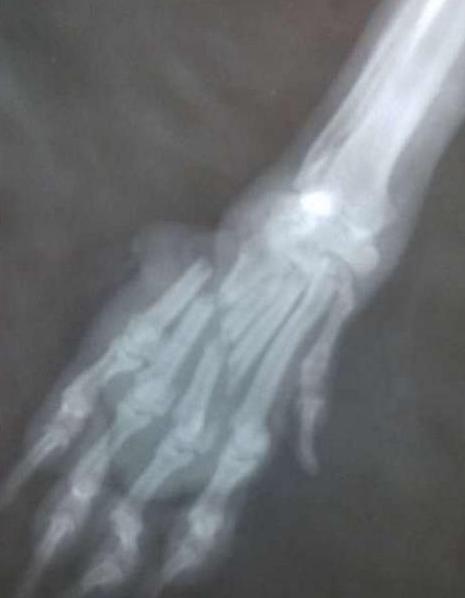

顾不得追究是谁做的,房子的新主人连忙叫来村民一起将狗狗送完了医院。但是在医院检查的时候,却发现,狗狗的四肢是被人呈水平切断的,非常难以续上,而且由于伤口感染,可能狗狗此刻最好的处理方法便是截肢。